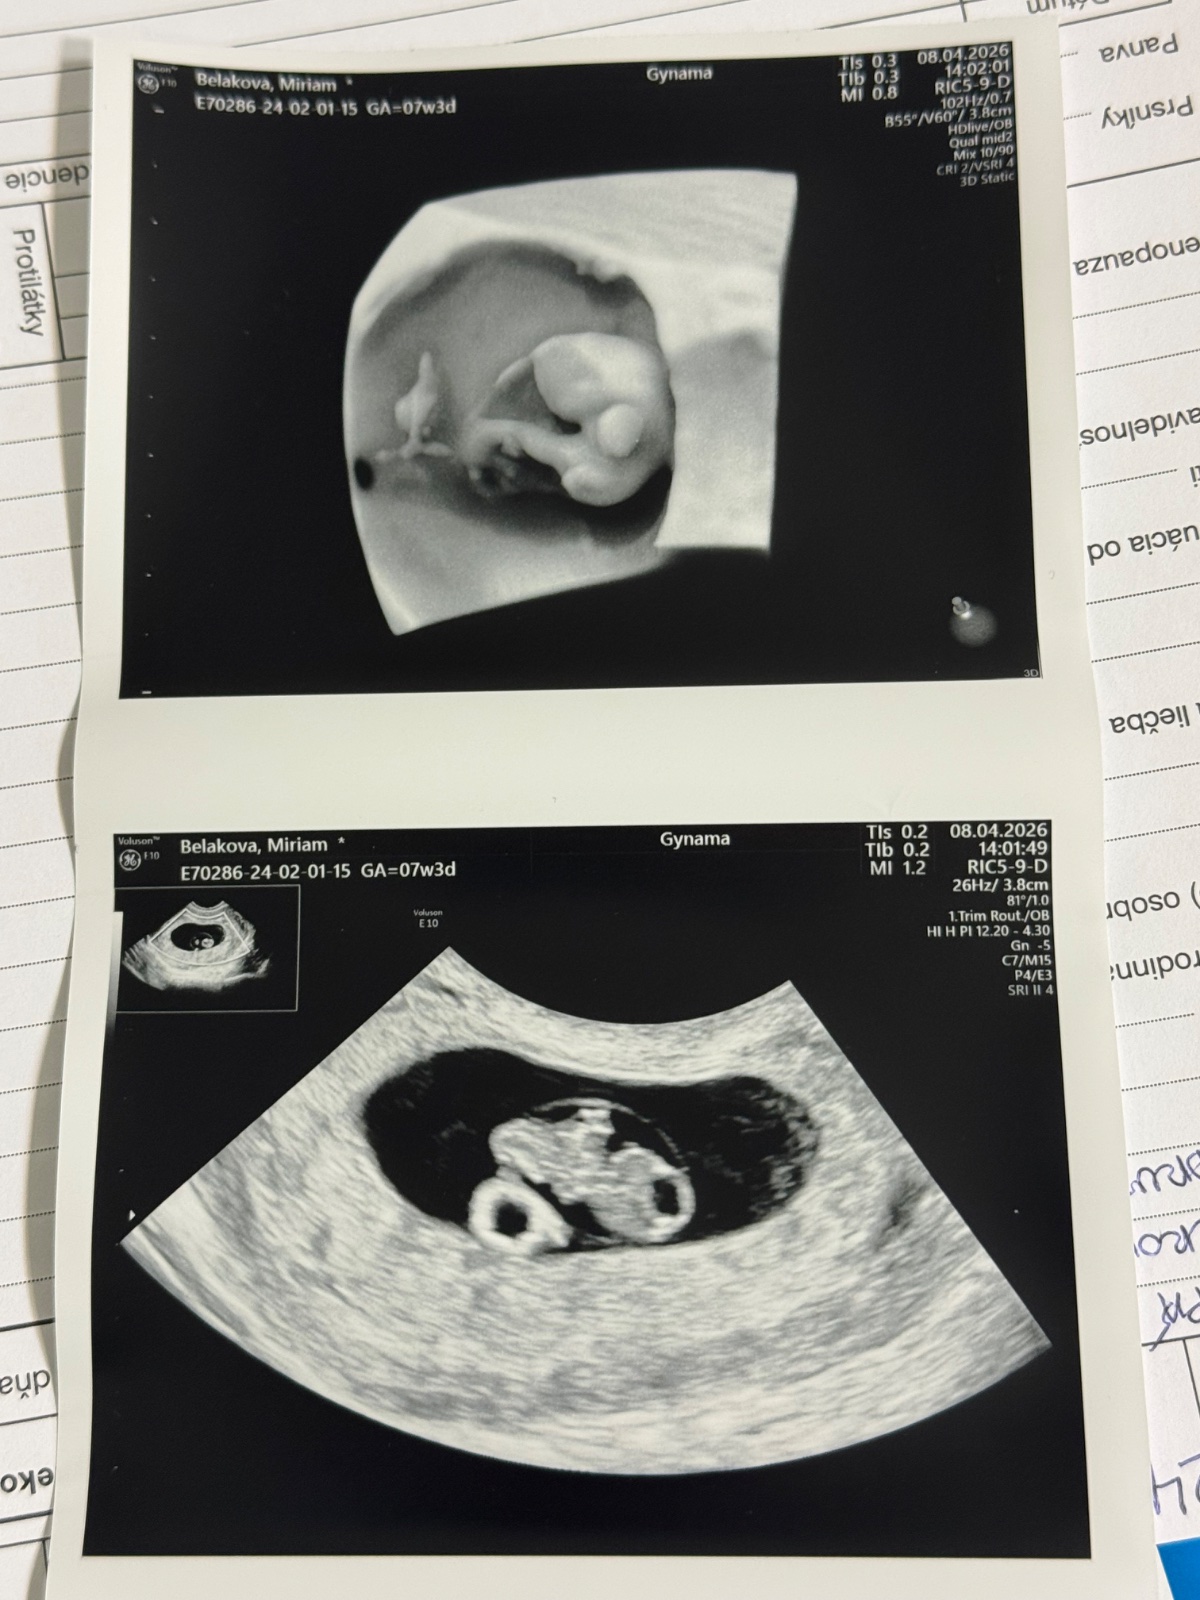

Prvý ultrazvuk: Možné určenie pohlavia dieťaťa?

No ženy jedna pozitívnejšia nez druha 🤣. Niesom tak debilna že viem že tam je moje meno, kľudne sa ním pokochajte možno nájdete aspoň moje podnikanie pod mojim menom - reklama keď ste už také šikovne, a podľa umiestnenia “vaku” je myslená Ramzi teória možno ste o tom ešte nepočuli niektoré ženy áno práve preto som sa pýtala či niekto skúšal podľa toho pohlavie zisťovať a ci to nejakej mamičke podľa tejto teórie vyšlo 🤷♀️ nevadí nechajte tak tu sa neoplatí nič pýtať v dnešnej dobe ešte aj na tehotenstve inej ženy sa robia posmešky

Jedine z vesteckej gule 🙂 Ani v 16tt si lekari nie vzdy su isti a to ma babo okolo 9-10cm, a tvoje mimi ma zatial iba 1,5cm. Dolezite je zdravie, nie pohlavie